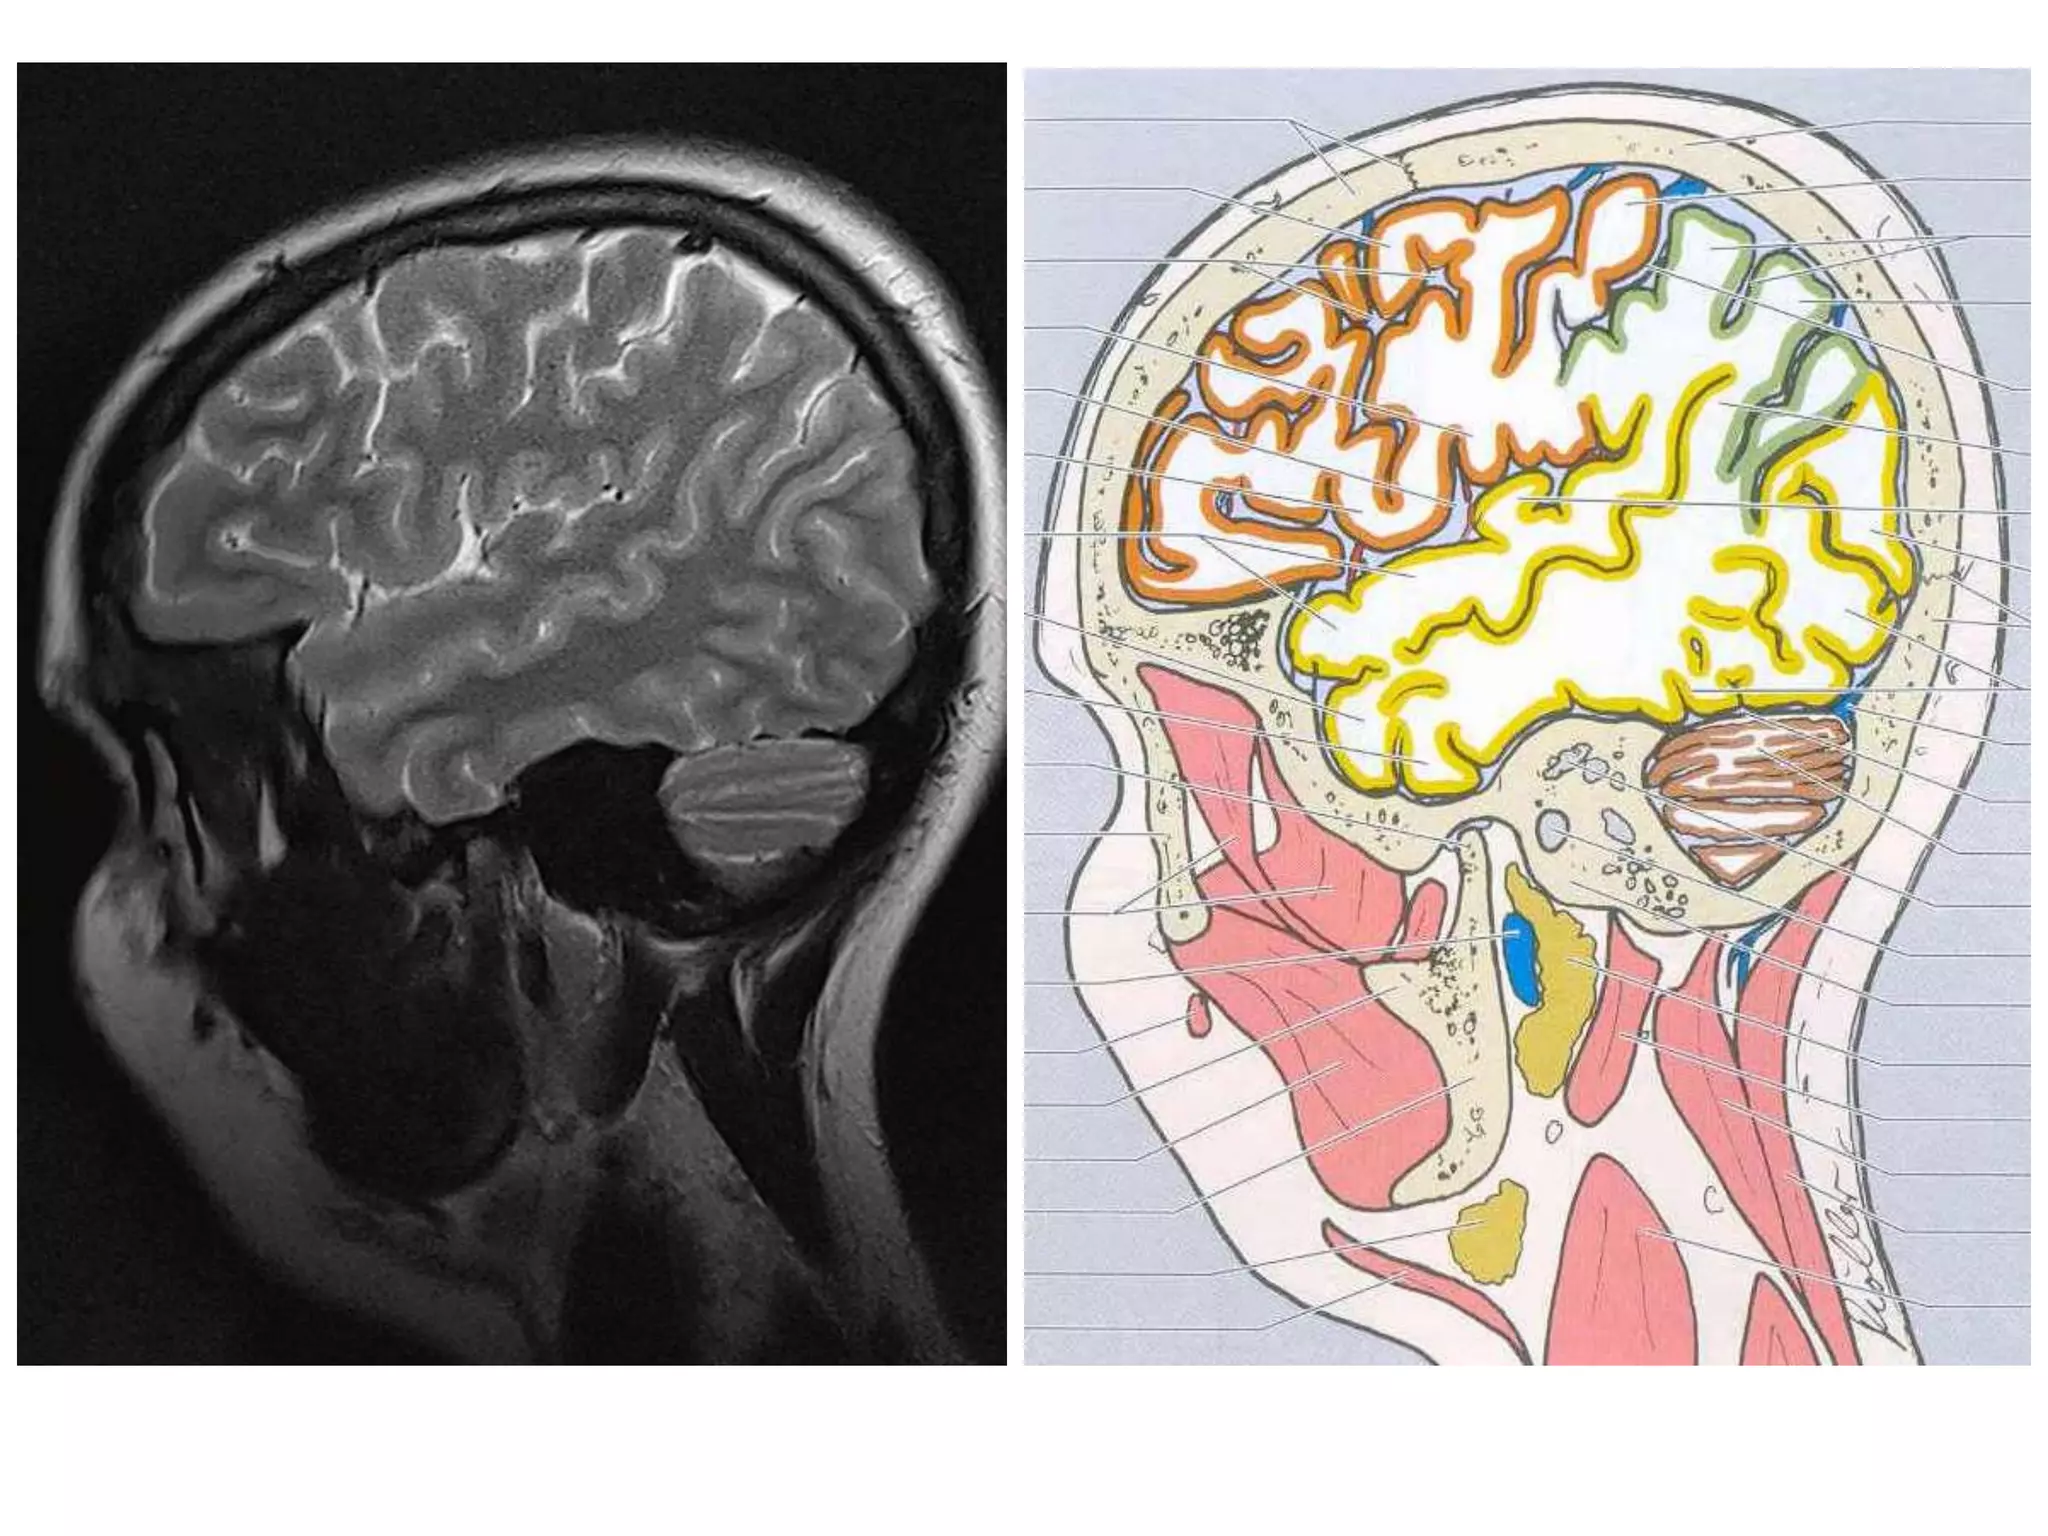

• Anatomy of cerebral hemispheres and mid brain – T1 W

MRI.

• Internal grey - white matter areas – T2 W MRI.

• Saggital and Coronal T1 weighted MRI – accurate

assessment of ventricles and C. callosum